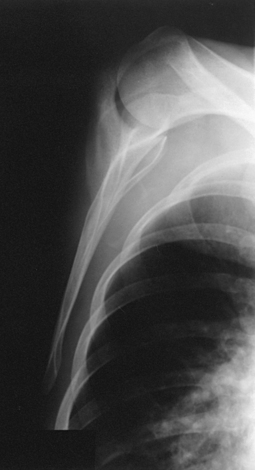

This projection, described by Rubin et al.,1 obtained its name as a result of the appearance of the scapula. The body of the scapula forms the vertical component of the Y, and the acromion and coracoid processes form the upper limbs. This projection is useful in the evaluation of suspected shoulder dislocations.

Structures shown: The scapular Y is shown on an oblique image of the shoulder. In the normal shoulder, the humeral head is directly superimposed over the junction of the Y (Fig. 5-37). In anterior (subcoracoid) dislocations, the humeral head is beneath the coracoid process (Fig. 5-38); in posterior (subacromial) dislocations, it is projected beneath the acromion process. An AP shoulder projection is shown for comparison (Fig. 5-39).